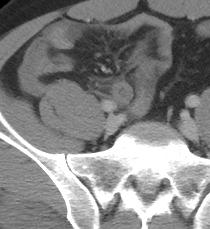

Se realiza búsqueda intencionada de la región de fosa iliaca derecha, apreciando una imagen tubular, en fondo de saco de ciego y presenta estriación de la grasa periapendicular la cual mide 10 mm en sentido anteroposterior, con presencia de un apendiculito en su interior de 5 mm, con densidad de 279 UH.

HALLAZGOS EN RELACION A PROCESO APENDICULAR AGUDO, CON APENDICOLITO EN SU INTERIOR, SIN EVIDENCIA DE LIQUIDO LIBRE..

- HALLAZGOS EN RELACION A PROCESO APENDICULAR AGUDO, CON APENDICOLITO EN SU INTERIOR, SIN EVIDENCIA DE LIQUIDO LIBRE..